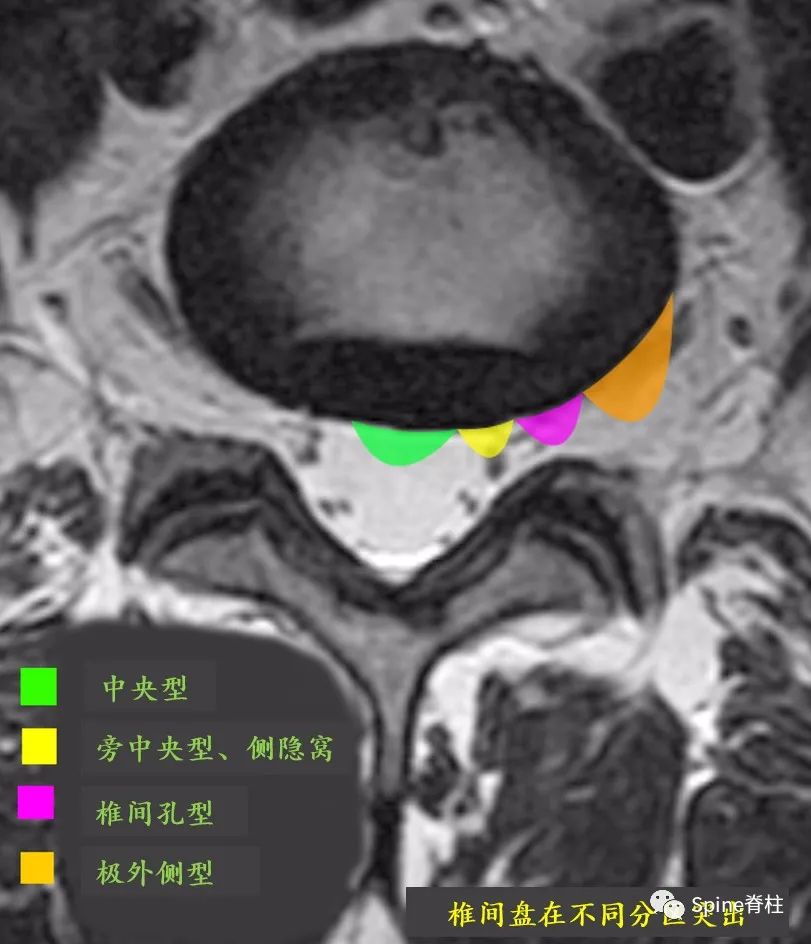

我们常说的腰椎间盘突出,其实指的是髓核的突出。 因椎间盘突出的类型、位置、大小及周围炎症、症状耐受反应不同,其临床表现也不尽相同,关键要看突出的椎间盘对脊神经和/或马尾神经的影响大小 (图6-8)。因此,同样是腰椎间盘突出,有些人可能痛不欲生,而有些人却是安然无恙。

图6A:不同类型的腰椎间盘突出

图6B:不同位置的腰椎间盘突出(横断面)

图6C:不同位置的腰椎间盘突出

(冠状面,图片来自网络)